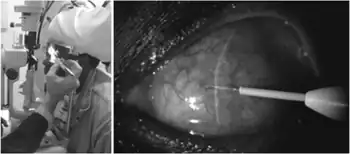

Subconjunctival injection is a type of periocular route of injection for ocular drug administration by administration of a medication either under the conjunctiva or underneath the conjunctiva lining the eyelid.

Using the subconjunctival injection bypasses the fatty layers of the bulbous conjunctiva and putting medications adjacent to sclera that is permeable to water, this will increase the penetration of the water-soluble drug into the eye.[1]